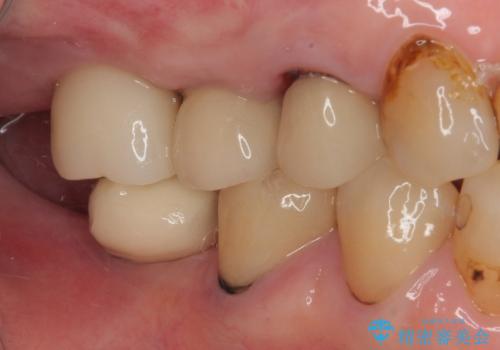

破折して抜歯となった奥歯 抜歯即時埋入・即時荷重インプラントによる補綴治療

埋入時に十分な安定値が獲得でき、埋入した際に仮歯を装着することができました。

術後の経過は安定しており、抜歯から3ヶ月で治療を終えることができました。